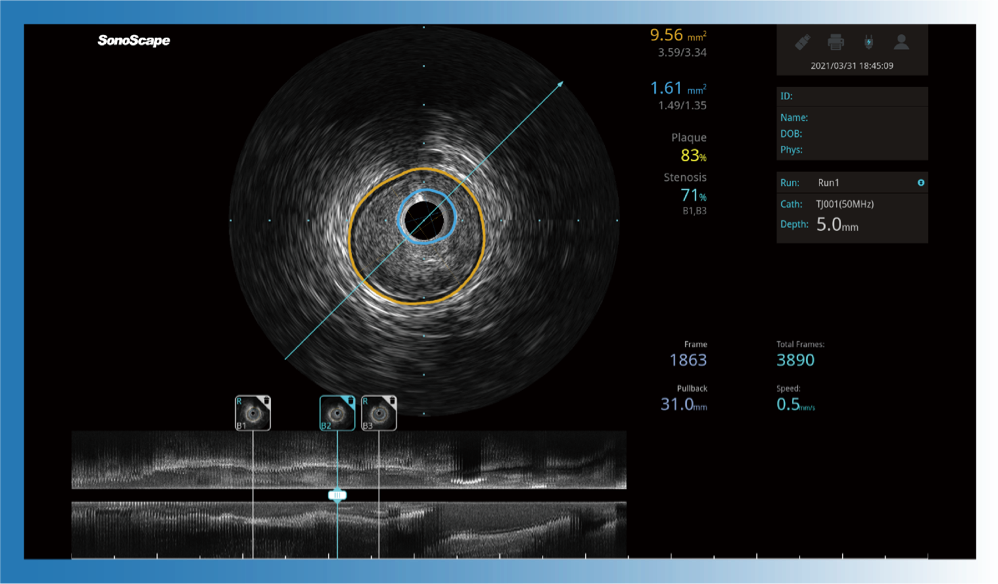

开立宽频IVUS图像

传统IVUS图像

对比传统IVUS导管成像,开立宽频IVUS图像的近场支架梁显影更细腻,远场中膜外血管仍清晰可辨,兼顾远中近,兼顾分辨力与穿透深度

一键智能描迹,自动测量斑块负荷、面积狭窄率等指标,准确率高于90%